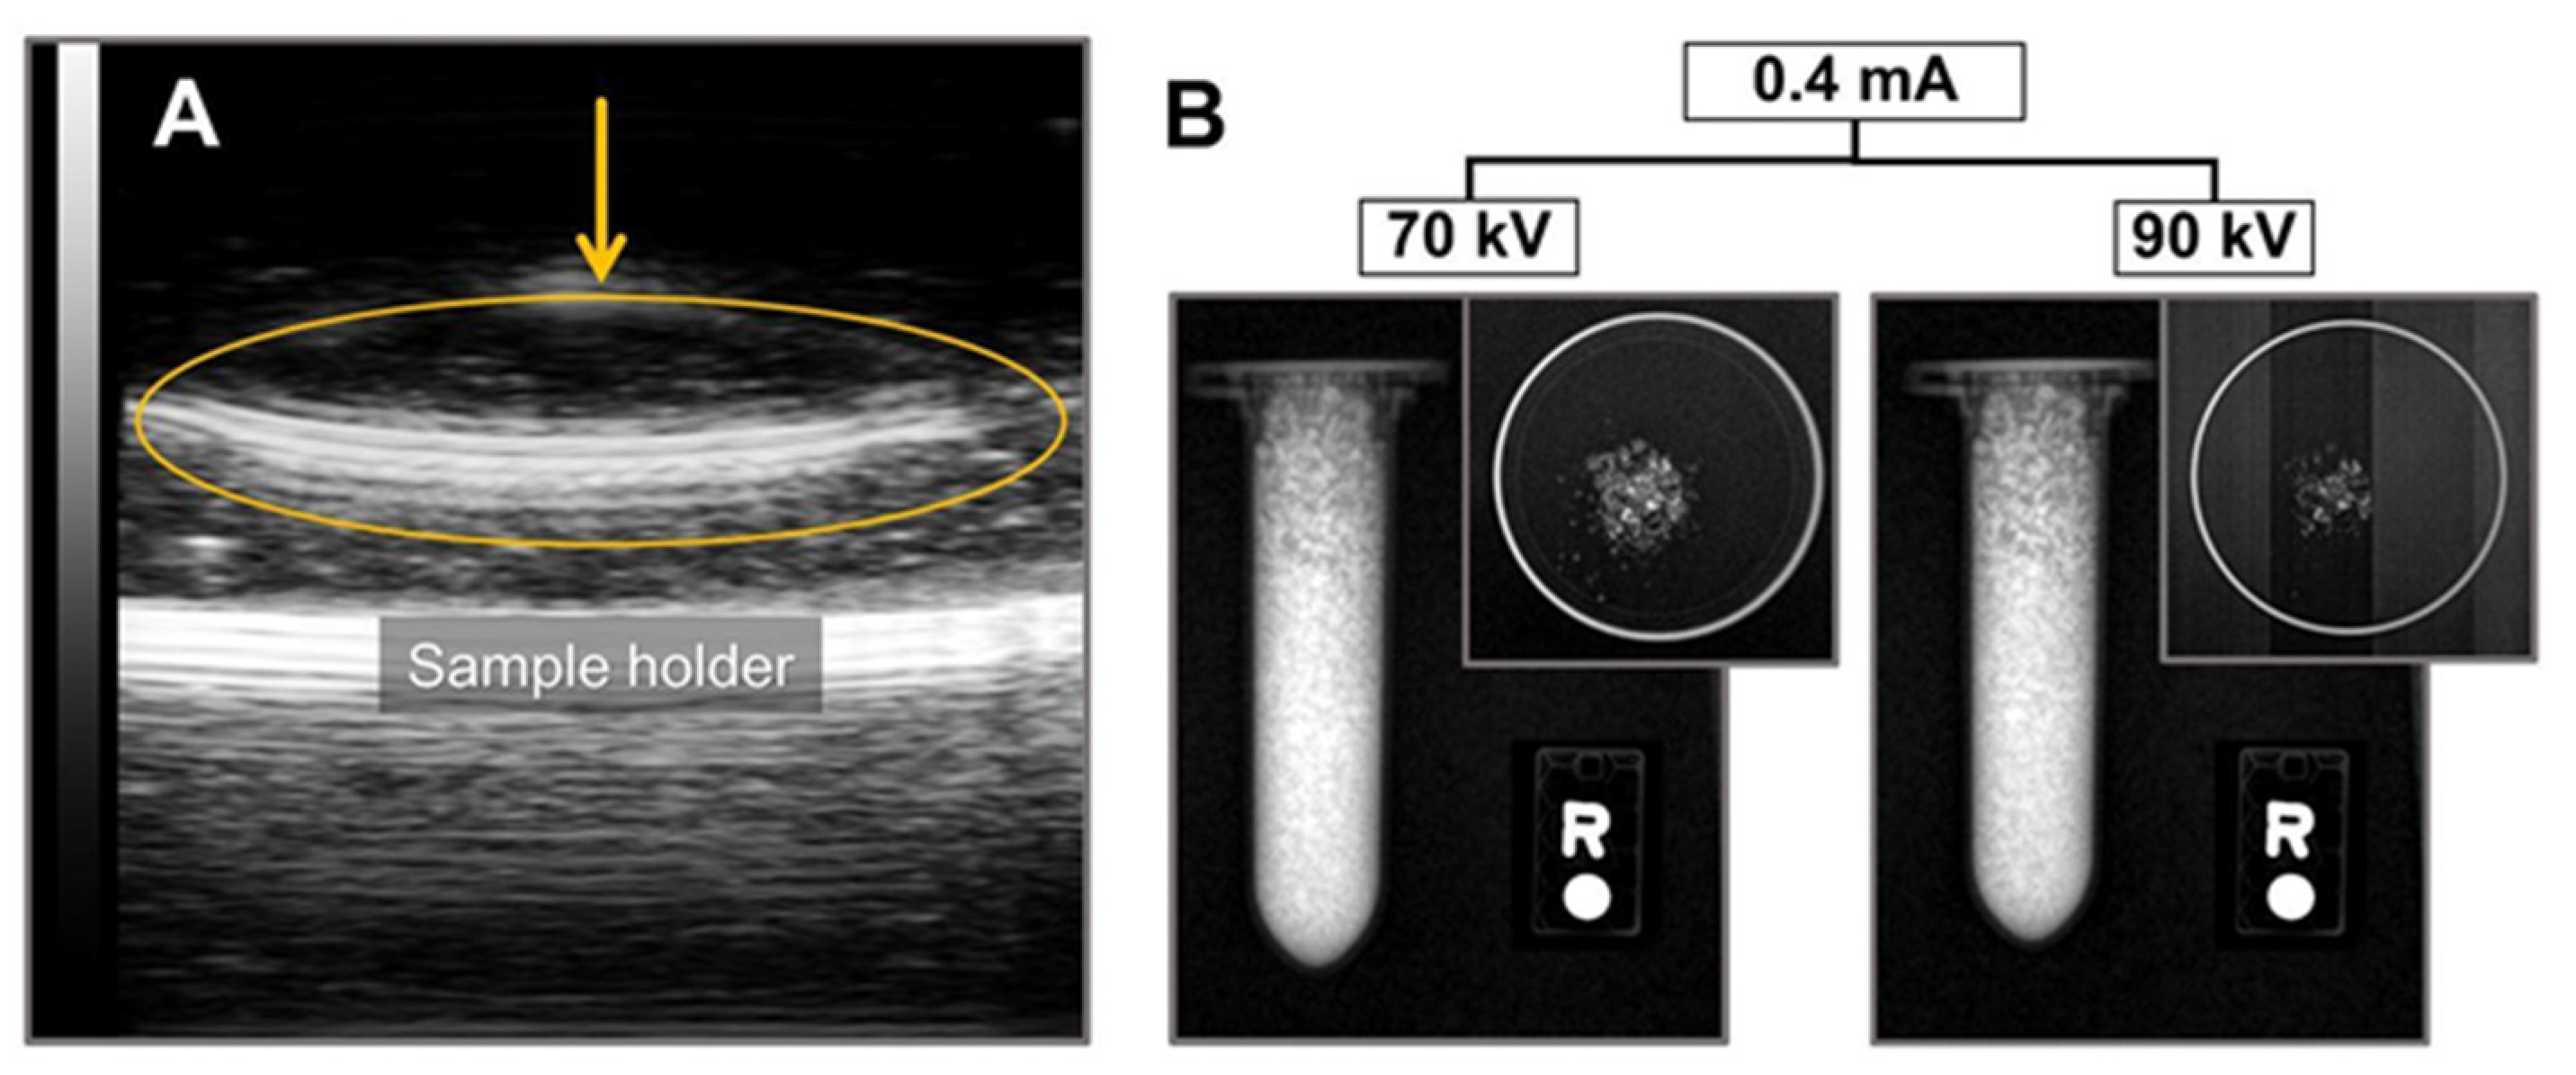

2.3. Ultrasound and X-ray Imaging

3.4. Ultrasound and X-ray Imaging Using Part-CaF2